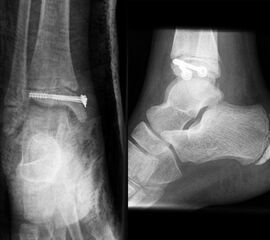

Behandlungsziel ist die exakte Rekonstruktion der Gelenkfläche sowie die Minimierung des Risikos einer späteren Wachstumsstörung. Dislozierte Frakturen werden offen reponiert, die Osteosynthese erfolgt mit einer Kleinfragmentschraube. Finden sich viele kleine Fragmente kann eine K-Draht Osteosynthese durchgeführt werden. Wird der Innenknöchel operiert, kann bei gleichzeitiger hochgradiger lateraler Instabilität eine Rekonstruktion des lateralen Bandapparats durchgeführt werden. Fibula Frakturen stellen sich meist spontan ein, sodass hier keine zusätzliche Osteosynthese notwendig ist.

Nach der Osteosynthese wird die Fraktur für ca. vier Wochen in einem Unterschenkelgips ruhiggestellt. Bei Schmerzfreiheit der Frakturzone erfolgt anschließend eine schmerzadaptierte Belastungssteigerung über weitere zwei Wochen. Sobald unter Alltagsbedingungen Beschwerdefreiheit besteht kann die sportliche Belastung langsam gesteigert werden. Kirschnerdrähte werden 6-8 Wochen postoperativ, Schrauben nach zwölf Wochen entfernt. Es empfiehlt sich klinische und radiologische Kontrollen im Abstand von 6 Monaten bis zum Wachstumsabschluss durchzuführen, um ein mögliches Fehlwachstum frühzeitig zu erkennen.

Dislozierte Frakturen (Frakturspalt > 2 mm) werden grundsätzlich operativ behandelt. Die Reposition kann arthroskopisch unterstützt erfolgen. Die Schraubenosteosynthese erfolgt entsprechend dem Frakturverlauf. Bei Twoplain Frakturen ist meist eine epiphysäre Schraube ausreichend die von lateral kommend das Fragment nach medial-proximal fixiert. Der Schraubenverlauf ist üblicherweise von lateral ventral nach proximal dorsal medial (Abb. 24). Nach Reposition darf in der seitlichen Aufnahme des Sprunggelenks, als auch in der 45° Außenrotationsaufnahme keine Stufe in Höhe der Wachstumsfuge erkennbar sein. Eine sichtbare Stufe ist Indikator für eine unzureichende Reposition.